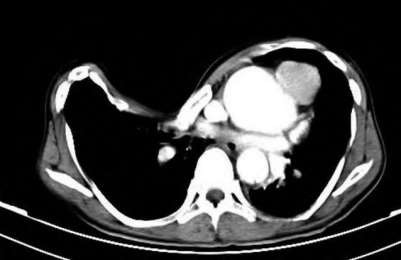

Contrast enhanced MRA of the wrist is typically used to diagnose hypothenar hammer syndrome or other vascular abnormalities.

A 20-year-old park ranger trips and falls onto his right wrist with the wrist in extension and pronation. The local urgent care orders both radiographs and a CT, which you review and determine to be normal. The patient complains of ulnar-sided wrist pain. On exam, his tenderness is localized to the fovea. Ulnar deviation also causes him pain. There is no snapping sensation with wrist supination, flexion, and ulnar deviation. He otherwise has 5/5 strength to his first dorsal interosseous muscle with 4mm static two-point discrimination on the ulnar side of the 4th digit. Which of the following injuries is most likely responsible for his symptoms and exam?